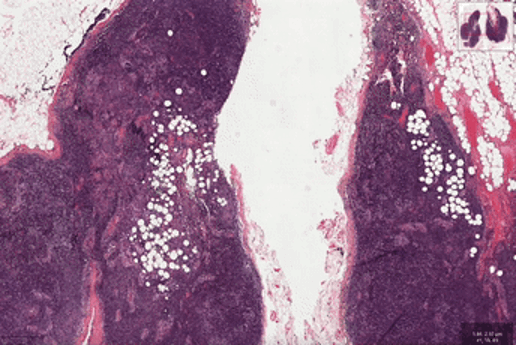

喏,拿一张病理全片扫描图像,不用遍历所有高倍镜视野,也能找到病灶所在。

在这之后,交到医生手里的往往是一张几万乘几万像素、甚至更高的高分辨率图像,能达到每个像素 0.25 微米。

医生要做的就是在这幅布满密集细胞和组织的超大尺寸图像中,肉眼找到风险的病灶位置并进行判断,可谓是“大海捞针”了。

第一个,尽管病理图像(WSI)具有十亿像素大小的高分辨率,却往往只有一个图像级标签。

目前绝大部分的方法都依赖于在高倍镜下对全切片进行密集采样的方式进行特征提取,并对所有采集特征进行信息整合进而实现全片诊断,工作量可想而知。

第二呢,这些图像的病变区域往往很稀疏。现有的方法大多依赖于多实例学习框架,需要在高倍率下密集采样局部的图像块(patch)。

这不仅增加了计算成本,还导致了诊断相关性弱、数据效率低下,一张切片往往需要几十分钟才能完成计算。

从结果上看,绝悟 RLogist 的优势非常明显。研究人员选择“淋巴结切片转移检测”及“肺癌分型”两个全片扫描图像的分类任务进行了基准测试。

结果表明,与典型的多实例学习算法相比,“绝悟RLogist”在观察路径显著变短情况下,能够实现接近的分类表现,平均用时缩短至四分之一,决策效率提升 400%。